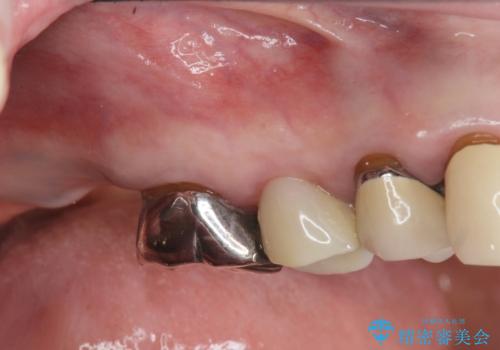

[ 破折し大きく吸収した歯槽骨 ] 他院では難しいと言われたインプラント治療

![[ 破折し大きく吸収した歯槽骨 ] 他院では難しいと言われたインプラント治療の症例 治療前](https://seimitsushinbi.jp/wp/wp-content/uploads/2024/10/073ce5e06775df372887a513b05b34d0-500x350.jpg?v=1729760111)